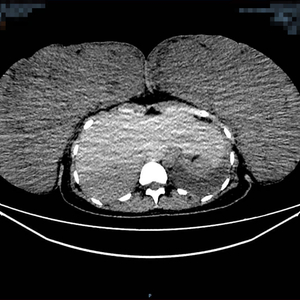

该患者胸部增强CT术前(左图)术后(右图)对比图,其中术前大小约:267mm×100mm×293mm(左),125mm×270mm×340mm(右)